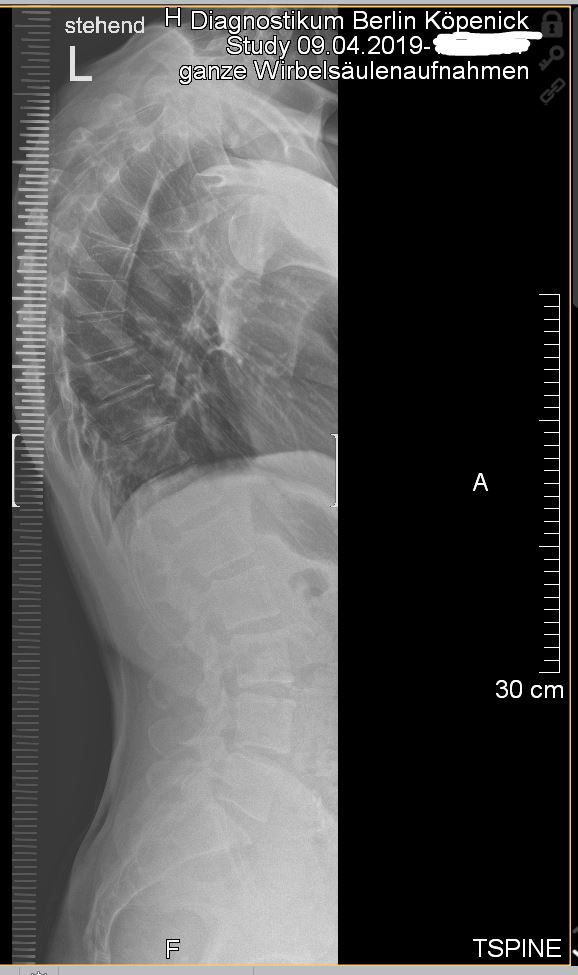

M4D24G Thorakalbereich; sonstige Lordose: Lumbalbereich;

"sonstige Lordose: Lumbalbereich":

M40.24 sein sollte, wäre "Sonstige und nicht näher bezeichnete Kyphose : Thorakalbereich" gemeint.

besonderen Verordnungbedarf" (früher Praxisbesonderheit) gehen sollte, müsste die Gradzahl der Kyphose auftauchen und ab 60 Grad wäre das bei Erwachsenen automatisch genehmigt, also auch bei Dir.